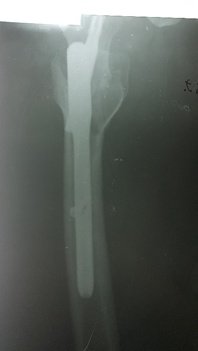

При огляді: положенння хворого пасивне на каталці, біль в області в\3 правої стегнової кістки та кульшового суглобу що посилюється при пальпації та спробі рухів у суглобі. Крепітація уламків. Права н\кінцівка ротована до зовні. Проведено рентгенографію правої стегнової кістки. Встановлено діагноз: Закритий уламковий, підвертельний перелом правої стегнової кістки (Клас АО 31.А3) зі зміщенням.

Хірургічної патології при поступлені хворого в стаціонар не виявлено.

Хворий госпіталізований в травматологічне відділення для подальшого дообстеження та оперативного лікування. З метою тимчасової фіксації, тракції та зменшення больового синдрому накладено систему скелетного витяжіння. В умовах травматологічного відділення хворий був дообстежений та оглянута суміжними спеціалістами терапевтом, анестезіологом.

Протягом 34 годин від отримання травми хворий був прооперований. Закрита репозиція з металоостеосинтезом перелому 31.А3 проксимальним стегновим стрижнем PFN-A-Long. Після оперативного втручання хворий перебував під наглядом у відділенні інтенсивної терапії. На 2гу добу хворий переведений в травматологічне відділення. В травматологічному відділення хворому під наглядом лікуючого лікаря було дозволено сідати у ліжку. На 3 тю добу хворий під наглядом лікуючого лікаря вставав на милиці. На 4-ту добу пересувався на милицях в межах палати. На 5 ту-10ту добу хворий пересувався з допомогою милиць в межах відділення. На 11 ту добу знято шви з рани. Хворий в задовільному стані виписаний з травматологічного відділення. На амбулаторне лікування. Надано рекомендації з приводу подальшого лікування в амбулаторних умовах.